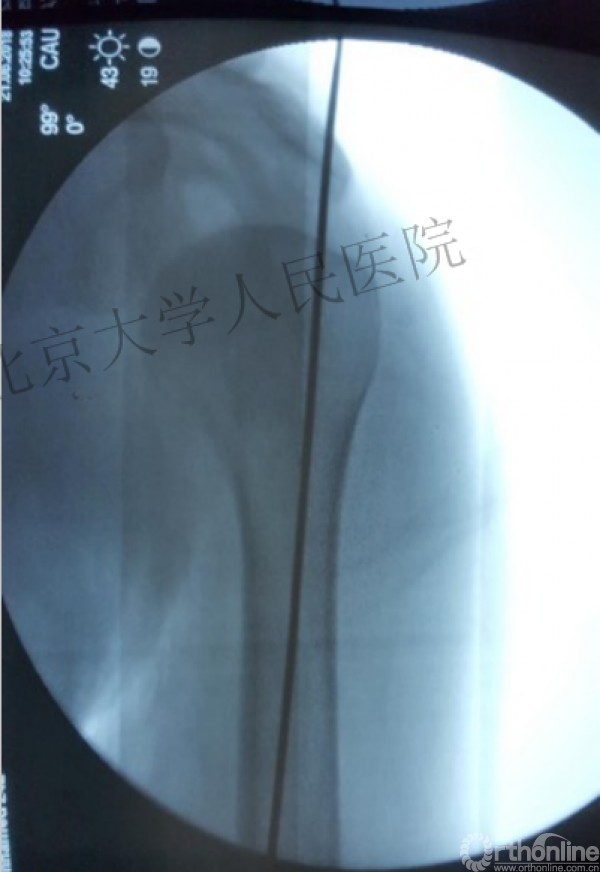

透视肱骨头正位、侧位确定进针点

好的进针位置是手术成功的标志!

复位良好的标准:颈干角:135°,大结节与肱骨头距离:8mm

进钉点的把握原则-最费脑筋的选址

进针点